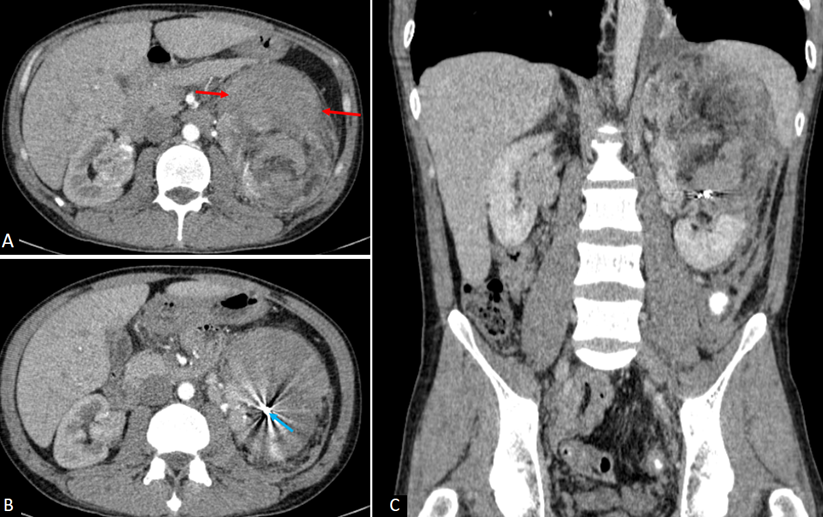

Sau thủ thuật, bệnh nhân có biểu hiện sốt nhẹ và đau tức bụng và được theo dõi kỹ tại khoa Ngoại Tiết niệu. CLVT bụng (hình 3) sau 3 ngày thấy khối máu tụ giảm kích thước và không còn xuất huyết hoạt tính. Vị trí của coil kim loại cố định không còn tưới máu. Khối u đã giảm đáng kể hình ảnh tăng sinh mạch. Sau 5 ngày, các triệu chứng cải thiện gần như hoàn toàn. Công thức máu có hồng cầu và hemoglobin tăng dần (Hồng cầu 4.66x1012/l và Hb 98 g/l). Bệnh nhân được xuất viện sau 10 ngày điều trị.

Hình 3. Cắt lớp vi tính bụng chậu sau can thiệp 3 ngày. Không thấy xuất huyết, không thấy mạch dị dạng trong u. Khối máu tụ quanh u (mũi tên đỏ) đã giảm kích thước đáng kể, không còn chèn ép tĩnh mạch thận trái. Mũi tên xanh chỉ coil nút mạch.